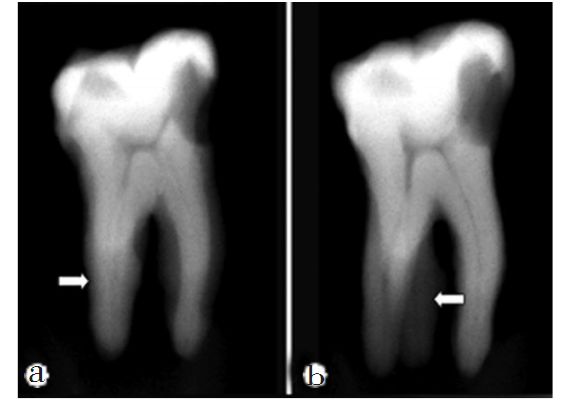

牙齒根管治療中如忽略根管治療,則會導致這個區域根管系統不可以完全清理工作嚴實添充,無法爲齲病和慢性牙髓炎痊愈給予最理想的標准,造成牙齒根管治療不成功。因而,根管治療忽略即是牙齒根管治療裏的錯誤操作之一,也是危害牙齒根管治療愈後的重要因素之一。